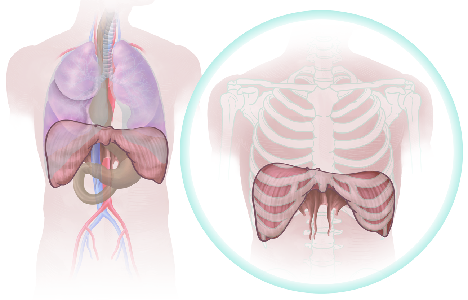

Detailreiche Fotografien aus der medizinischen Praxis ergänzen die Texte; moderne, genaue,

wissenschaftliche Zeichnungen geben Einblick in die Anatomie und die Funktion der Lunge und

anderer Organe.